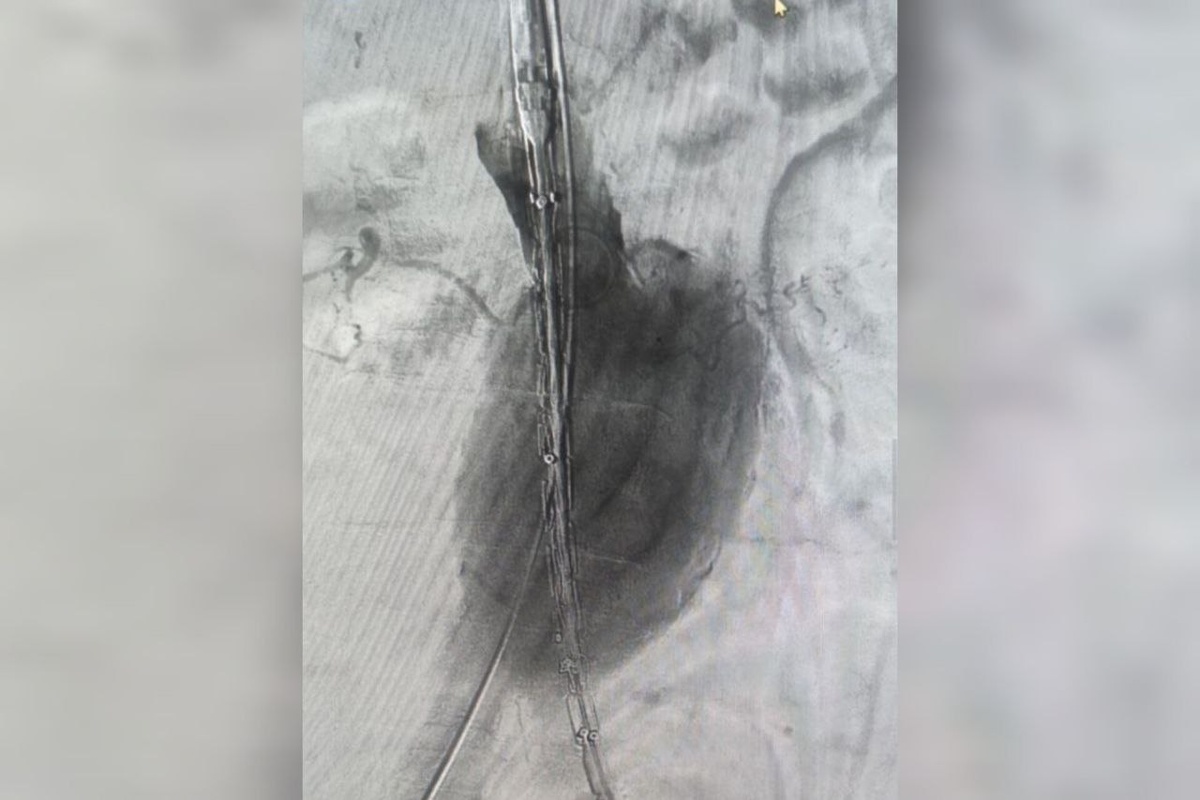

Фото: облздрав

В Волгоградской областной больнице №1 провели уникальную операцию по установке стент-графта для лечения аневризмы брюшной аорты.

У пациента был крупный размер аневризмы, создававший высокую угрозу разрыва. Кроме того, мужчина старше 70 лет и имеет тяжелые хронические заболевания. Поэтому было принято решение провести операцию, хоть и крайне рискованную.

Стент-графт укрепляет стенку аорты изнутри, создавая новый прочный канал для кровотока.

«Это решение позволяет полностью восстановить функцию магистрального сосуда и предотвратить жизнеугрожающие осложнения», – сообщили в облздраве.